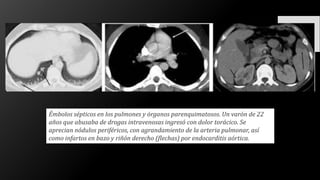

Émbolos sépticos en los pulmones y órganos parenquimatosos. Un varón de 22

años que abusaba de drogas intravenosas ingresó con dolor torácico. Se

aprecian nódulos periféricos, con agrandamiento de la arteria pulmonar, así

como infartos en bazo y riñón derecho (flechas) por endocarditis aórtica.